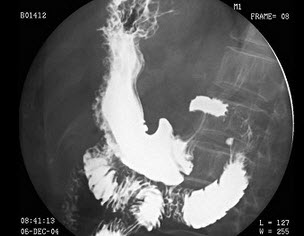

24、单项选择题

男,40岁,腹胀痛1月余。体检:脾肋下5cm,结合图像,最可能的诊断为()

A.正常食管

B.食管静脉曲张

C.食管胃底静脉曲张

D.贲门失弛缓

E.食管癌